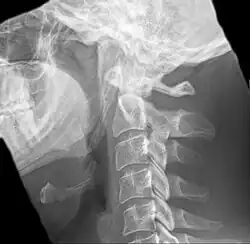

Radiograph, lateral view showing joint-like formation in ossified stylohyoid ligament -